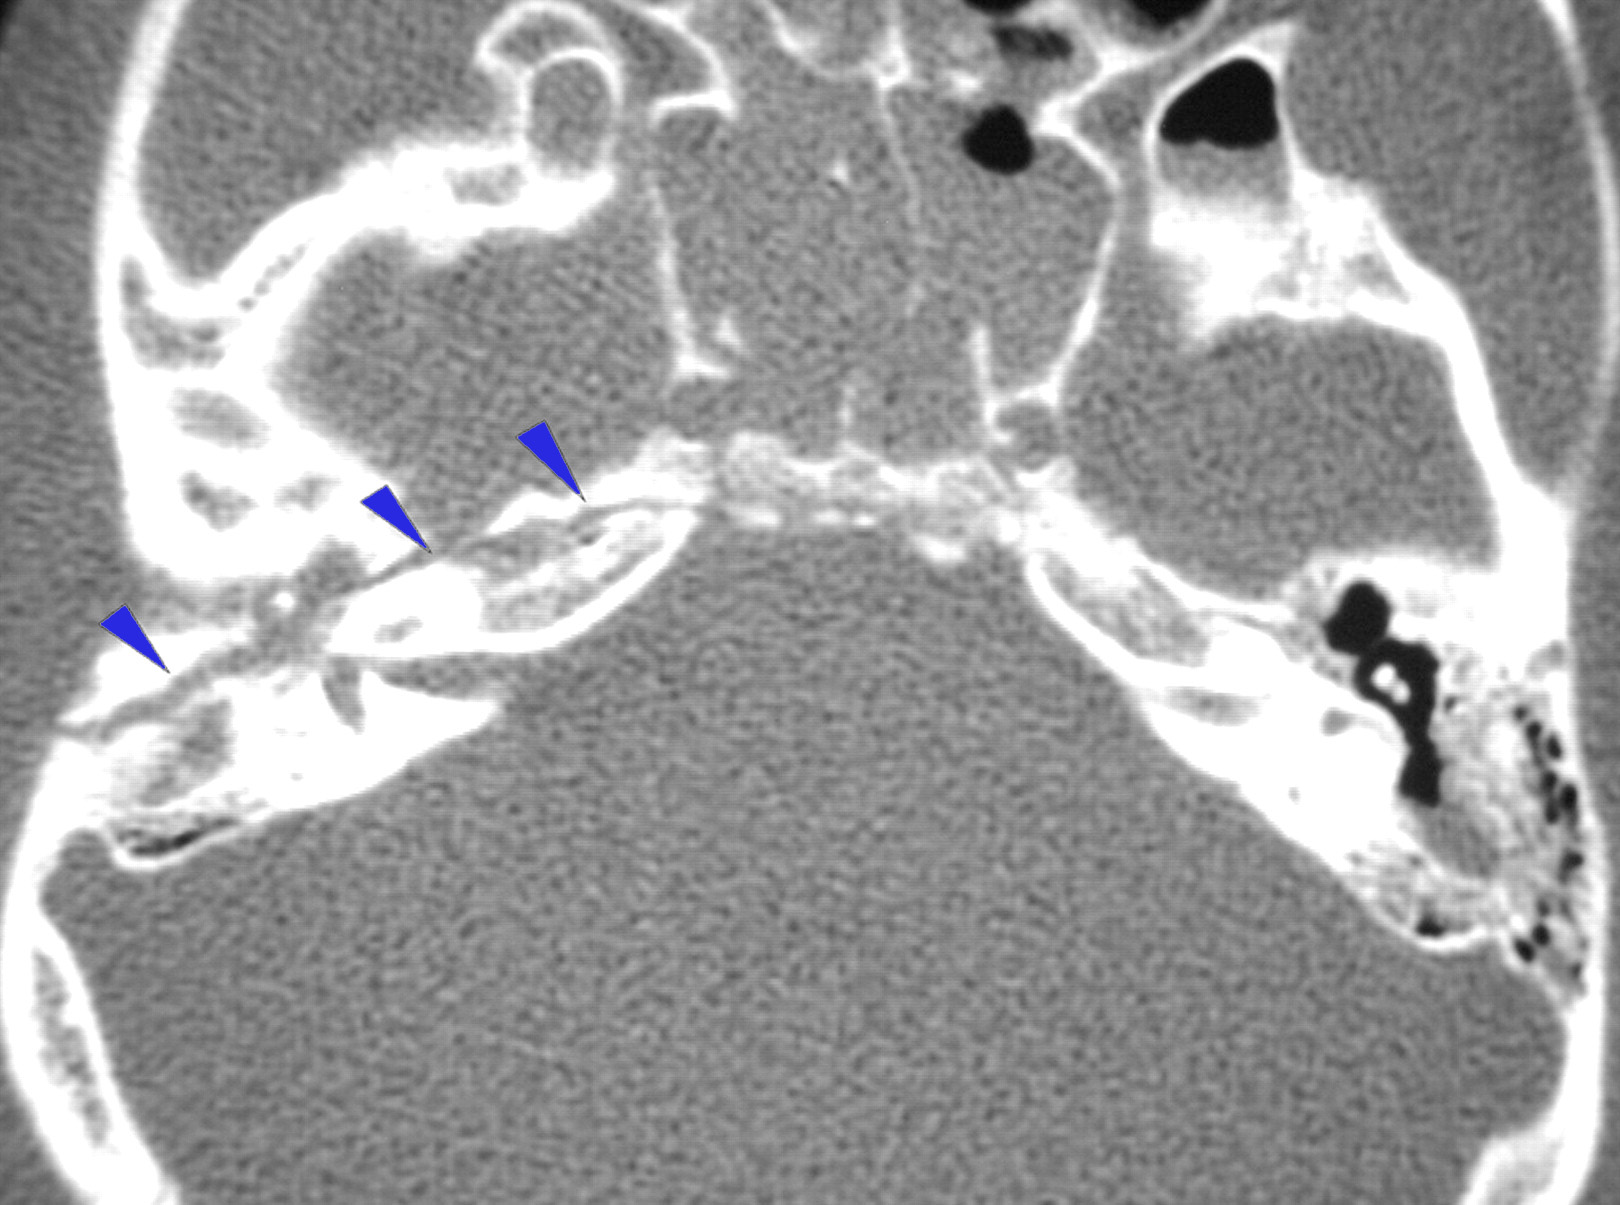

CT temporal bone image showing longitudinal fracture

The fracture line parallels the long axis of the petrous pyramid. It starts from the squamous portion of the temporal bone, extends through the postero superior portion of the external auditory canal, continues across the roof of the middle ear space, anterior to labyrinth to end anteromedially in the middle cranial fossa close to foramen lacerum and ovale.